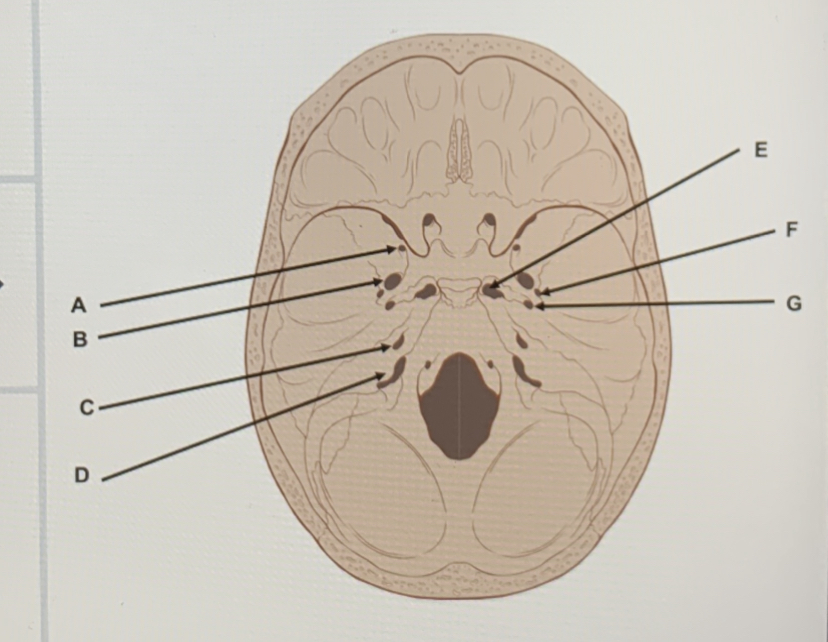

what is A

foramen retundum

what is B

foramen ovale

what is C

IAM

what is D

jugular foramen

what is E

foramen lacerum

what is F

foramen spinosum

what is G

carotid canal